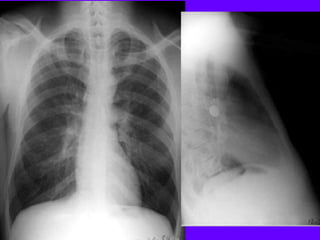

Consolidation / Lingula

Density in left lower lung field

Loss of left heart silhouette

Diaphragmatic silhouette intact

No shift of mediastinum

Blunting of costophrenic angle

Lateral

Lobar density

Oblique fissure not

significantly shifted

Air bronchogram